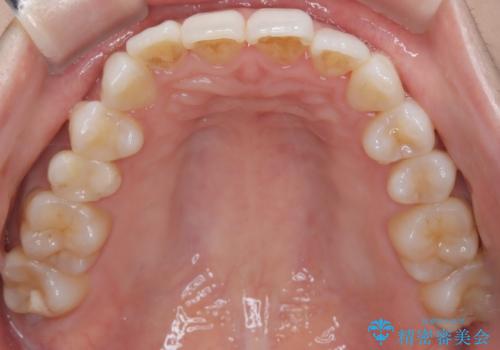

インビザラインモデレートによる前歯の叢生改善|IPR最小限で自然な歯並びへ

- 患者様は、**前歯の叢生(がたつき)**を気にされて来院されました。

診査の結果、中等度の叢生であったため、インビザラインモデレートでの対応が可能と判断しました。

前歯の叢生は解消され、自然で調和の取れた歯並びが得られました。